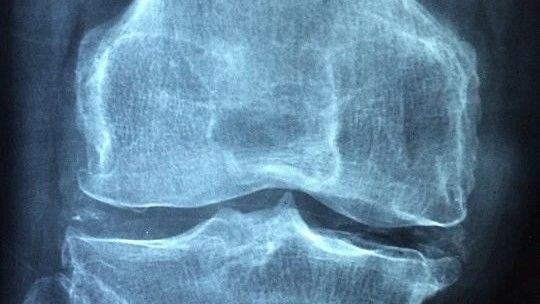

骨质疏松是因为缺钙导致的吗?

骨质疏松其实是一种全身性疾病,根据病因的不同可以分为三类,第一大类是与绝经、年龄大有关的,称为原发性骨质疏松,多见于中老年人。第二大类是与疾病或药物有关,称为继发性骨质疏松,常见的一些疾病如甲亢、1型糖尿病、肝胆疾病、类风湿、痛风、慢性肾病等,以及一些药物如糖皮质激素、肝素、甲氨蝶呤等,均会导致骨质疏松,这一类可见于任何年龄段。最后还有一类是特发性骨质疏松,与骨代谢调节异常有关,比如青春期生长,或者妊娠期及哺乳期,“需求”突增,骨形成和吸收的平衡被打破,也会导致骨质疏松。